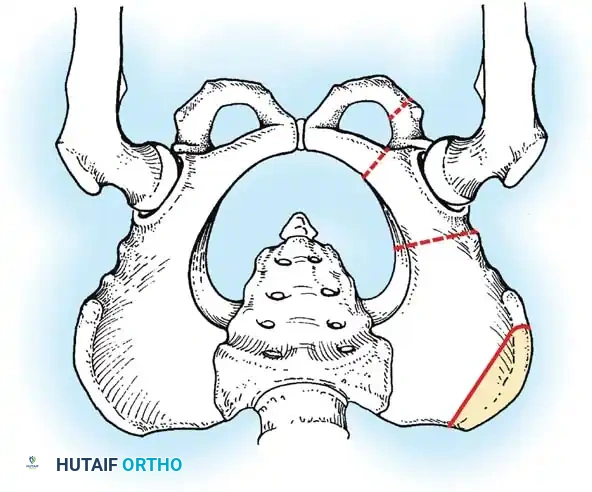

Diagrammatic representation of the Salter Innominate Osteotomy. Note the complete iliac cut and the placement of the triangular bone graft to redirect the acetabulum.

- Pemberton Pericapsular Osteotomy:

- Indications: Severe dysplasia with a capacious acetabulum.

- Biomechanics: An incomplete cut is made through the ilium, curving down to the triradiate cartilage, which acts as a hinge. This reshapes the acetabular roof, reducing its volume and improving anterolateral coverage.